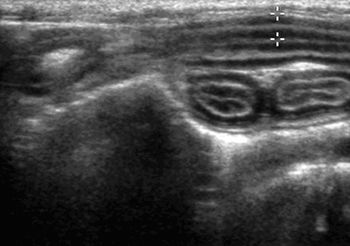

Ultrasound of the gastrointestinal (GI) tract has become an increasingly popular and useful diagnostic procedure for evaluation of gastric and intestinal disease.